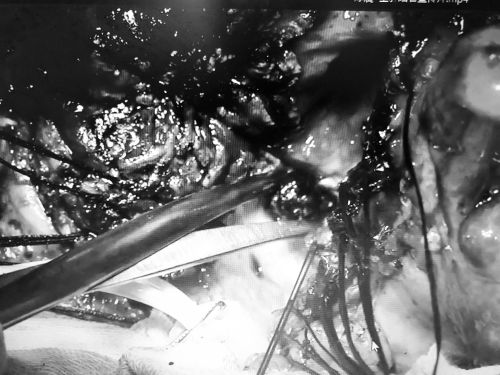

常规入肝途径不通,省医肝胆团队另辟蹊径不切肝取尽结石。图为医生用手术钳夹取结石。

术中取出结石251克。

在反复讨论病情、制订周密的手术方案后,7月24日,首席专家吴金术教授带领胆道外二科主任汪新天教授、陈晨副主任医师等,为患者施行手术。由于患者曾经做过手术,腹腔内粘连严重;经历过胆囊次全切手术,导致胆囊分离困难;右肝管狭窄,常规途径(肝圆韧带途径、胆囊床途径)无法进入肝脏;加上门脉高压、肝静脉回流障碍,仅仅切除30mm左肝方叶,出血就达到200ml。

在此情况下,手术团队只得另辟蹊径,采用胆管高位切开、肝门胆管成形、盆式内引流术,结合硬质胆道内镜钬激光碎石,解除肝门部胆管的狭窄,重建新的胆管流出通道,充分取出结石。经过近10个小时的手术,最终取出251g结石,创下近年捷克论坛